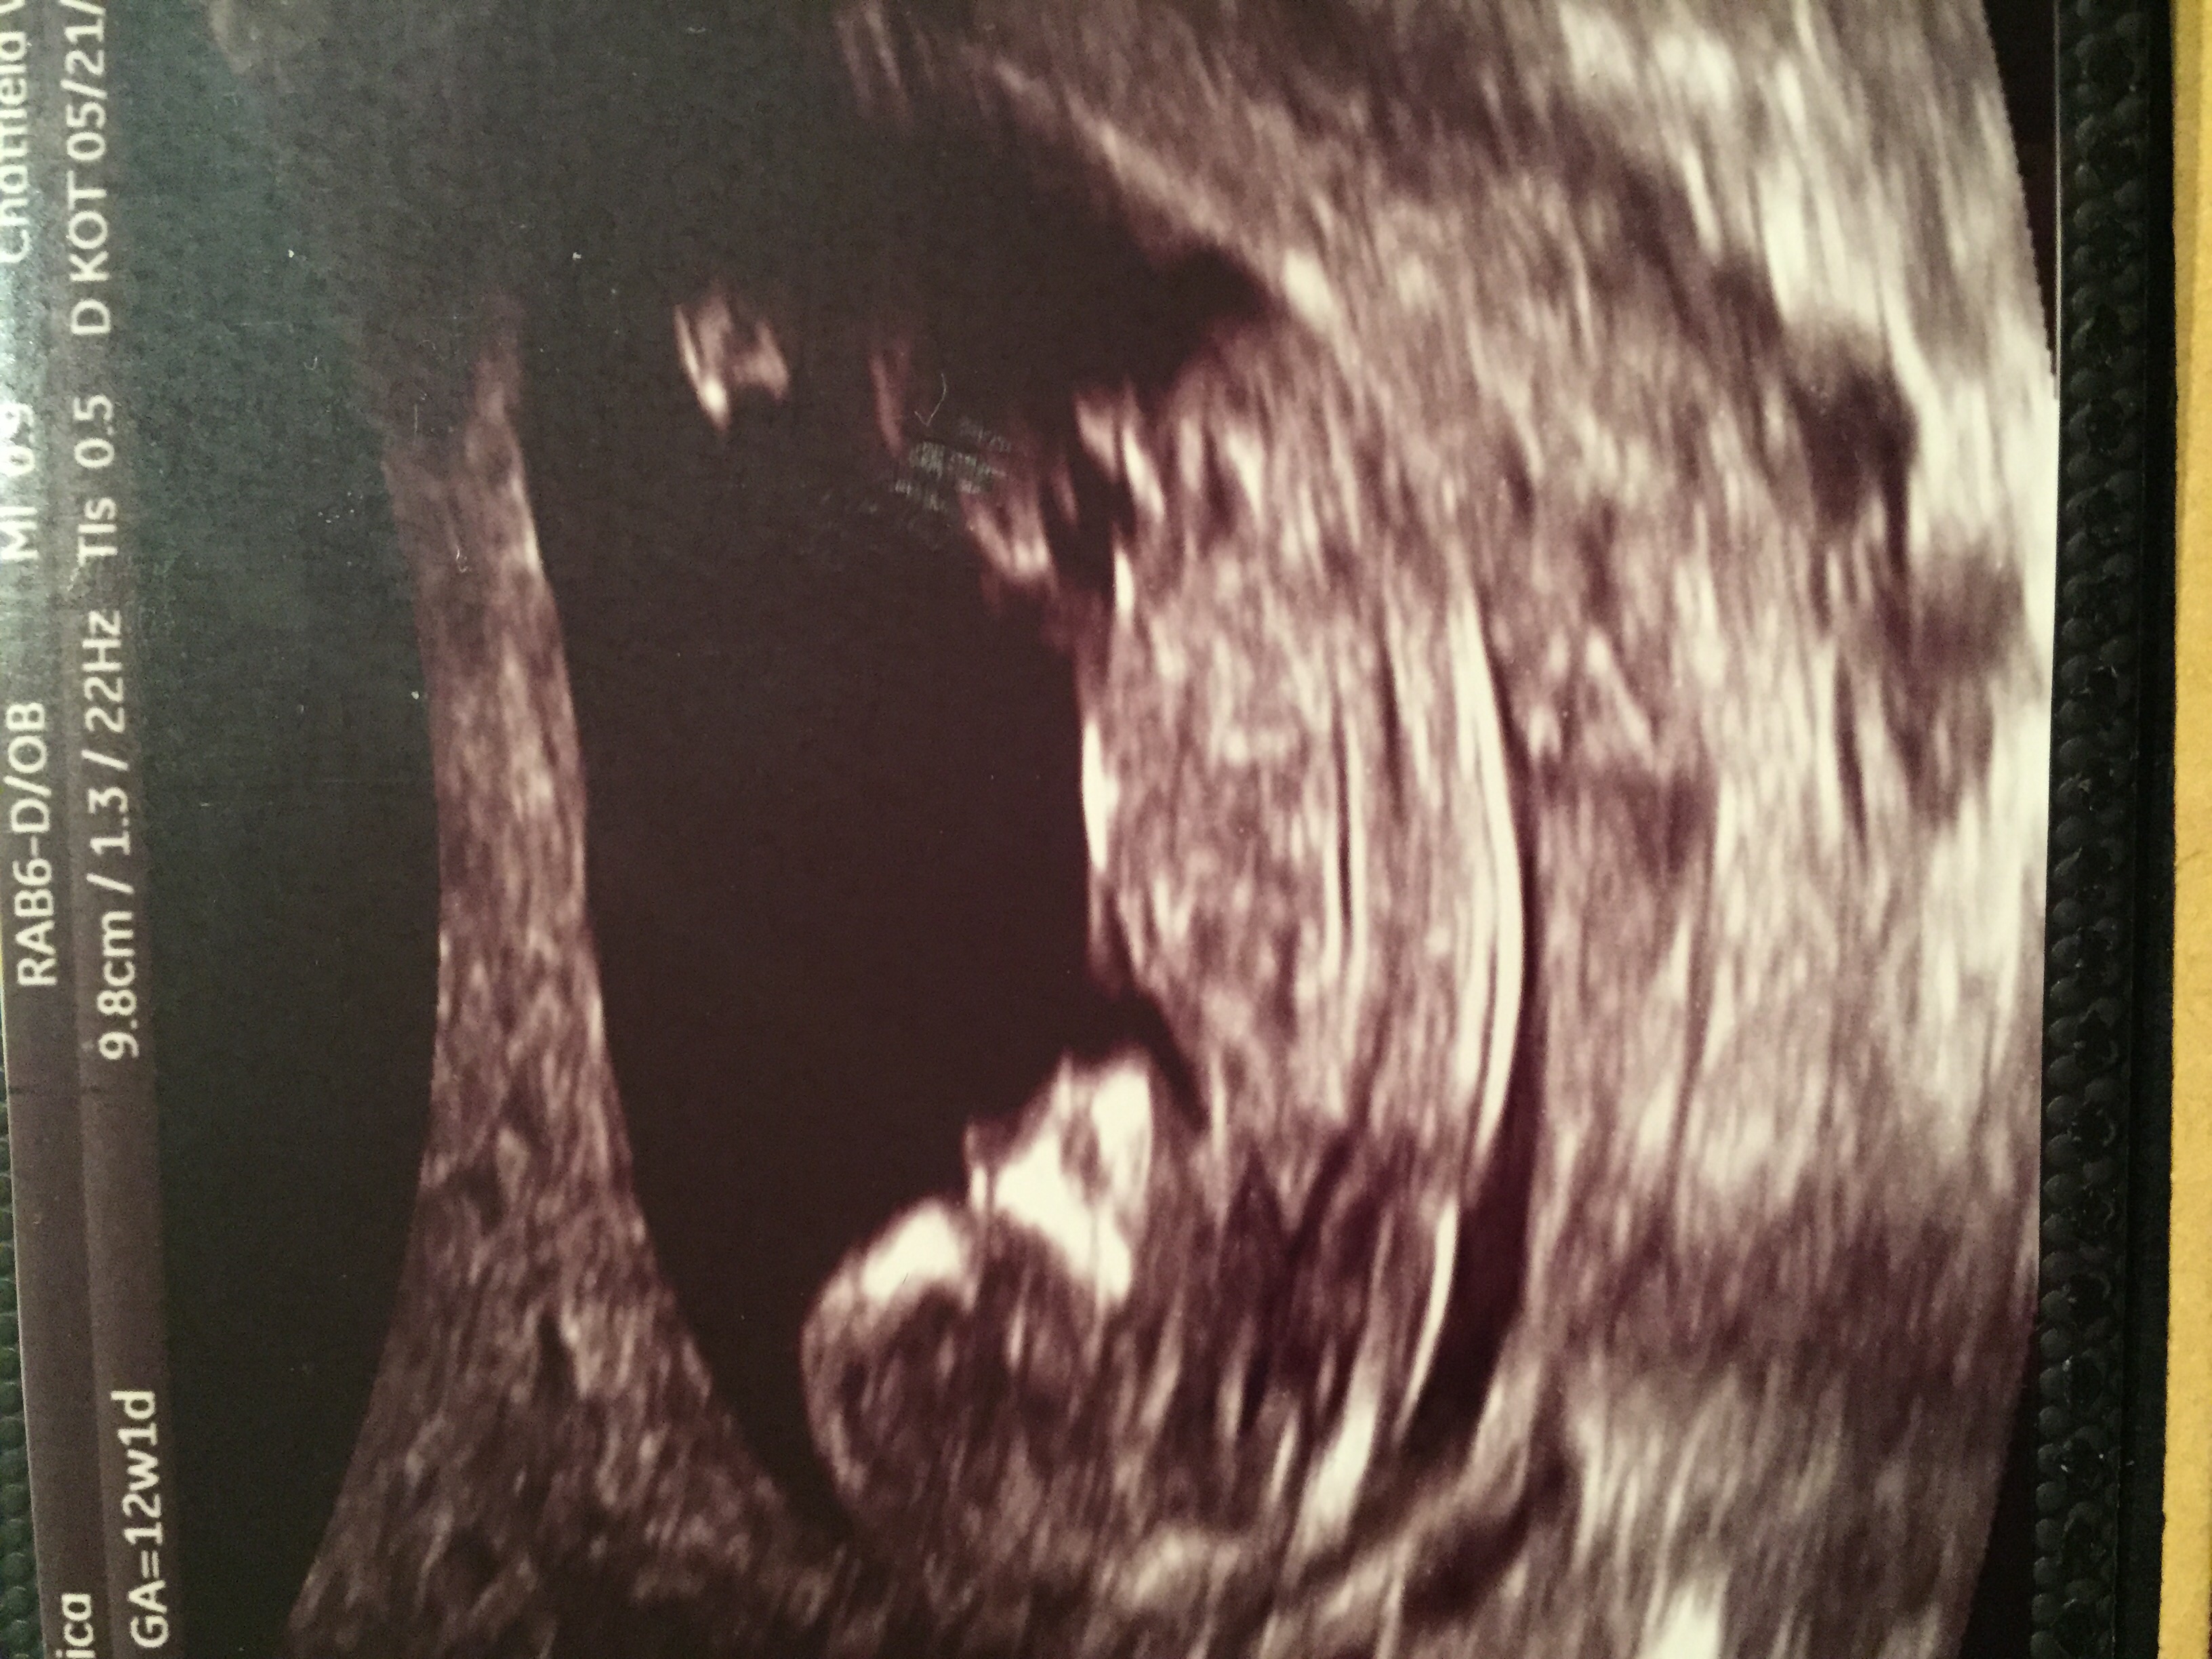

I already knew we were having a boy from the MaterniT21 blood test but we could clearly see the penis on today's ultrasound (12 weeks 3 days).

According to the nub theory it does have an angle so we are probably having a boy.